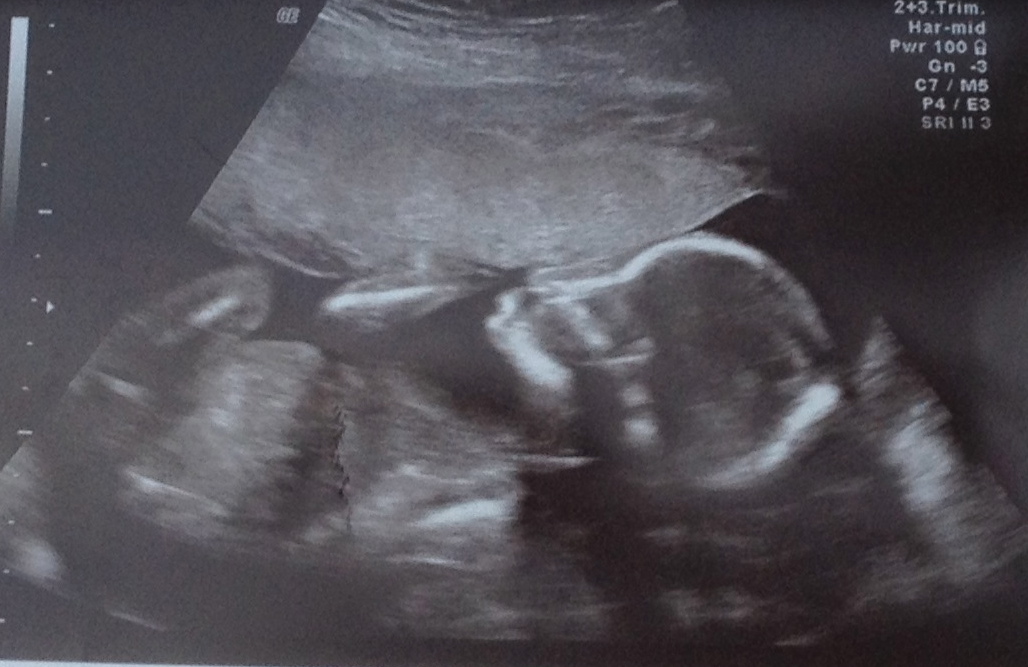

20 Week Scan Picture

We had our 20 week scan today and it was lovely to see bubs and everything is good which is great news :)

I personally can't see anything in the scan pics that might give me any clues but thought I would check with you guys too......

Anyone have any thoughts on the skull/gender etc??

No gender clues in the lower region...and that's a tricky skull. In one shot it looks boy, another girl. Looks like this bub wants to be team green too :))))))

great photos! I'm going to guess girl due to head shape its rounded more like a girl and looks like my daughters old scan photos!